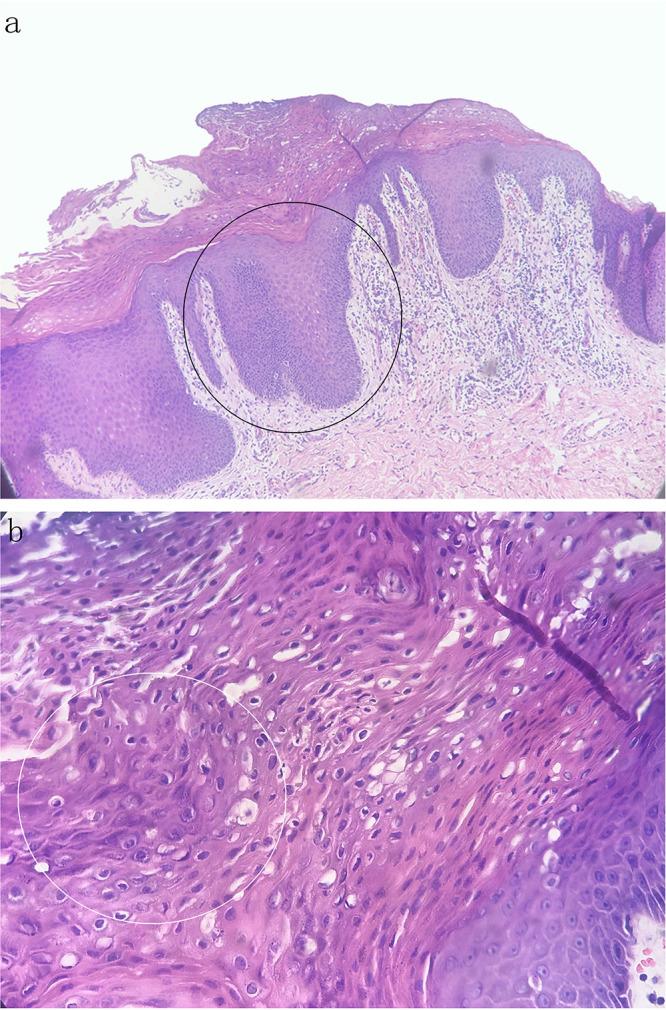

Granular parakeratosis is a rare dermatosis characterized by erythematous scaly patches or papules, and plaques, often involving intertriginous areas. In this work, a 73-year-old Chinese male patient presented with a 6-month history of pruritic verrucous papules on the bilateral groin. A skin biopsy was performed and revealed the following: the horny layer showed highly compact hyperkeratosis and parakeratosis with basophilic granules; the epidermis showed obvious acanthosis with psoriasiform hyperplasia. The final diagnosis was verrucous granular parakeratosis. We also reviewed the progress in nomenclature, etiology, clinical manifestations, differential diagnosis and treatment. Different clinical manifestations may represent different clinical entities. Dermatologists should differentiate it from other diseases to make a correct diagnosis. Treatment options should be based on the variable etiologies and clinical manifestations.

颗粒状角化不全症是一种罕见的皮肤病,其特征为红斑鳞屑性斑块或丘疹及斑块,常累及皮肤褶皱部位。在本研究中,一名73岁的中国男性患者双侧腹股沟出现瘙痒性疣状丘疹6个月。进行了皮肤活检,结果如下:角质层显示高度致密的角化过度和角化不全,并伴有嗜碱性颗粒;表皮显示明显的棘层肥厚伴银屑病样增生。最终诊断为疣状颗粒状角化不全症。我们还回顾了其命名、病因、临床表现、鉴别诊断及治疗方面的进展。不同的临床表现可能代表不同的临床实体。皮肤科医生应将其与其他疾病相鉴别以做出正确诊断。治疗方案应基于不同的病因和临床表现。